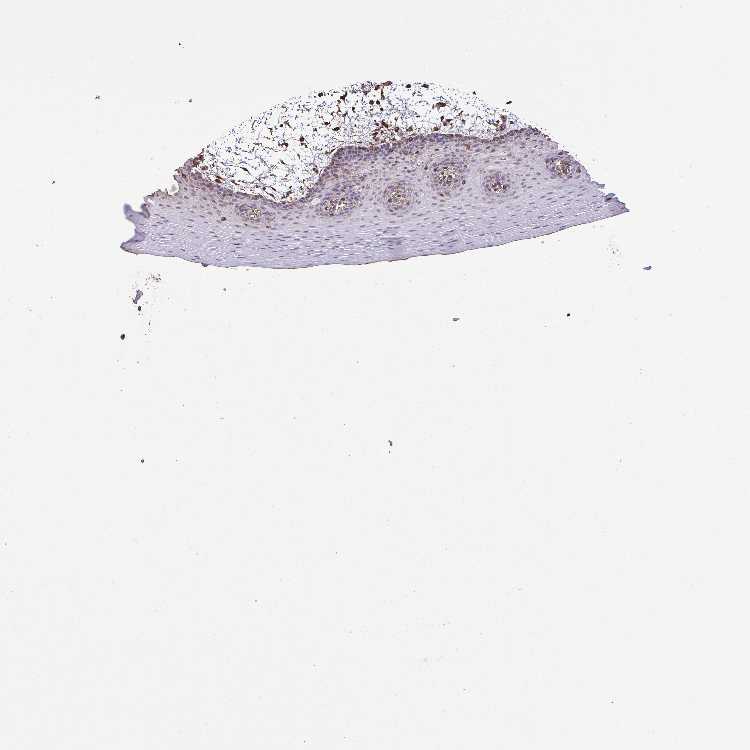

TISSUE PRIMARY DATA ORAL MUCOSA Show tissue menu

ORAL MUCOSA - Antibody stainingi

Antibody staining in the annotated cell types in the current human tissue is reported as not detected, low, medium, or high, based on conventional immunohistochemistry profiling in selected tissues. This score is based on the combination of the staining intensity and fraction of stained cells.

Each image is clickable and will lead to virtual microscopy that enables deeper exploration of all samples and also displays staining intensity scores, fraction scores and subcellular localization as well as patient and tissue information for each sample.

Antibody HPA035330Antibody CAB003677

Squamous epithelial cells Not detectedNot detected